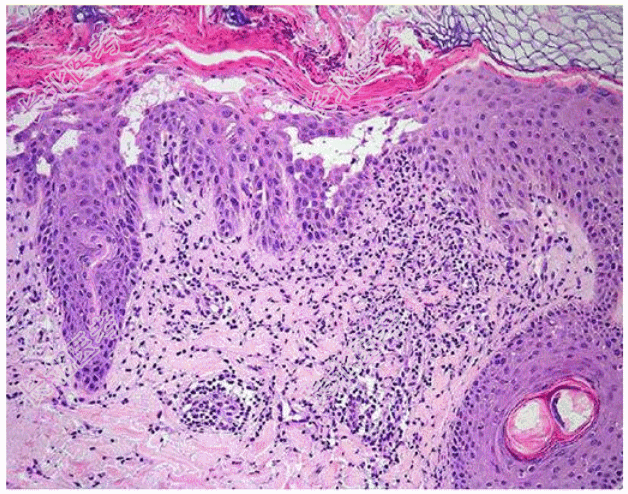

- [材料题] 患儿男,5岁,因“面部、胸部及躯干见对称性小丘疹”来诊。查体:面部、胸部及躯干见对称性密集的角化性小丘疹,粟粒大,皮色,坚实,表面被覆油腻性痂,去痂后可见丘疹顶端漏斗状凹陷。提示:光镜下组织形态如图所示。病理诊断为毛囊角化病。